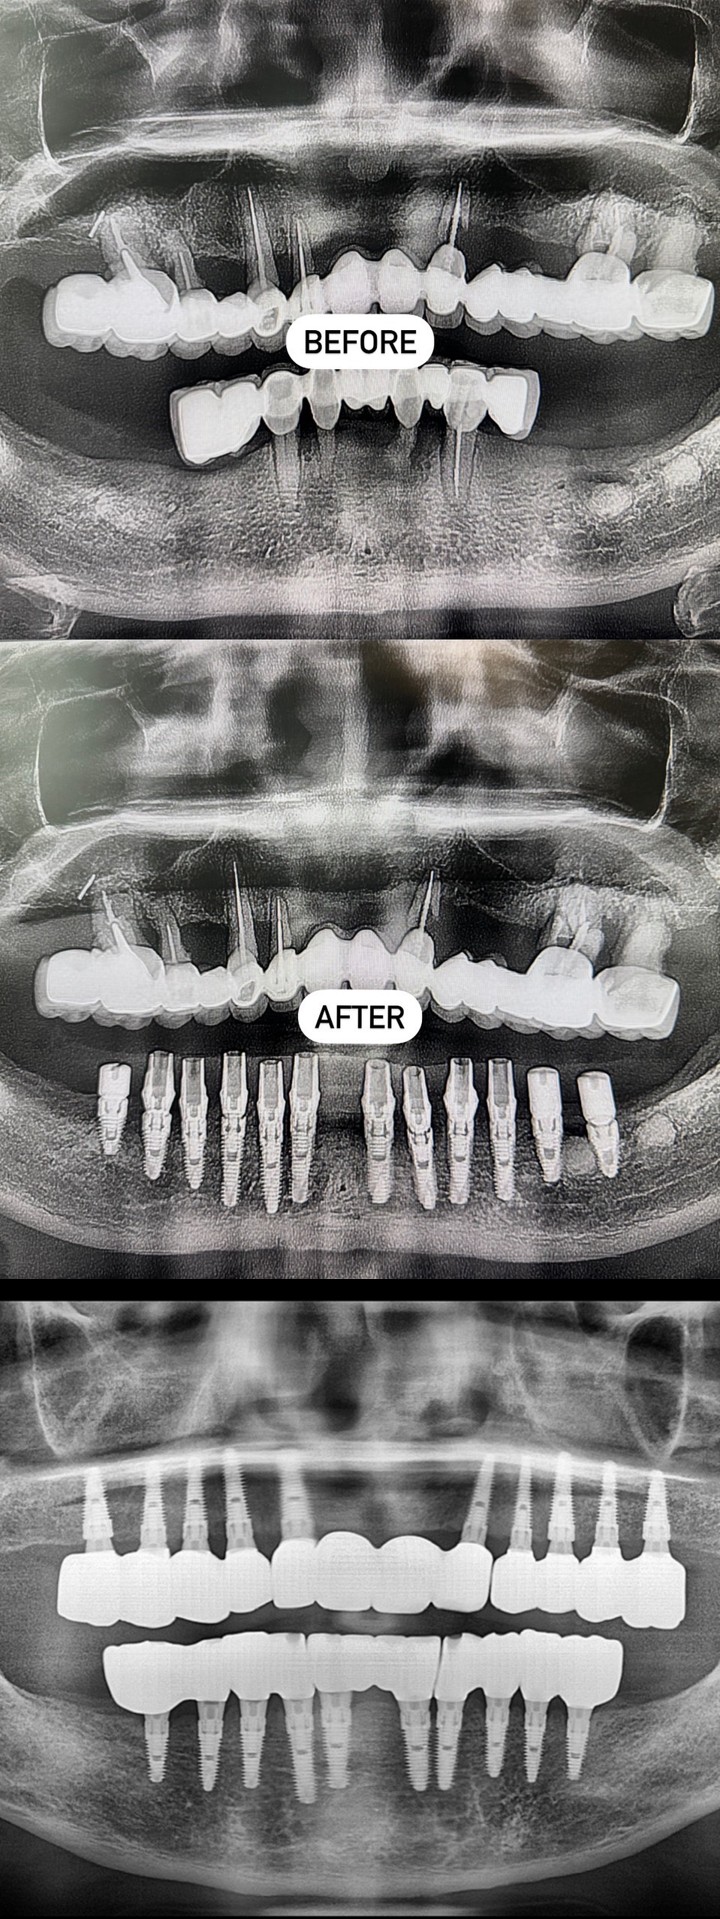

精奈創一鑽植牙系統團隊|手感與導板的取捨

這位病人的植牙滿兩年了,他非常認真照顧口腔健康,每三個月定期回診保養。

這為病人上週剛完成植牙,預計三個月後就能裝上最終假牙。

※ 若需使用影像 X 光片作為文宣或廣告,請事先聯繫並取得同意,感謝您的尊重!